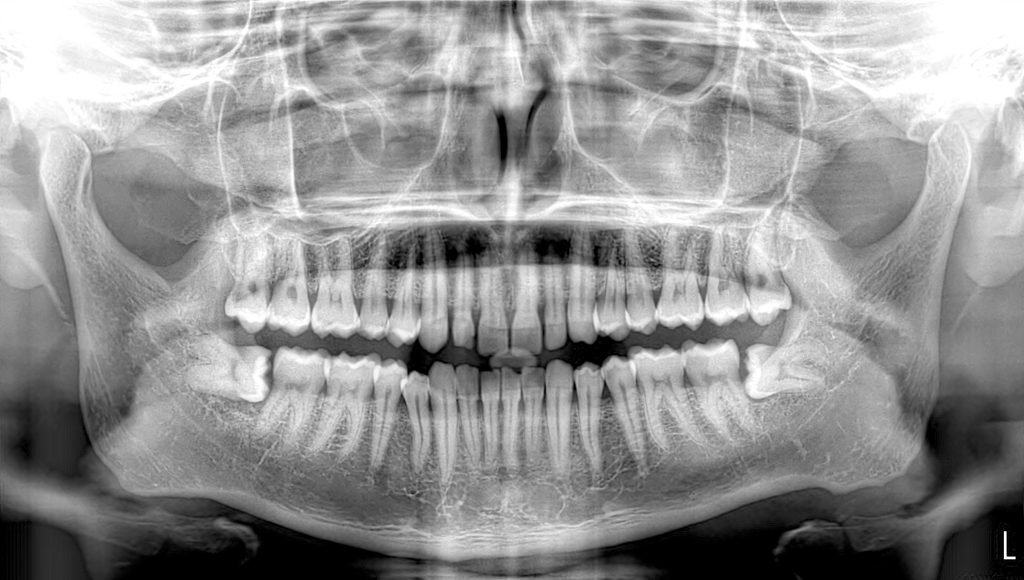

Impacted tooth extraction/Wisdom tooth extraction

Wisdom teeth are the third and final set of molars that most people get in their late teens or early twenties.

Sometimes these teeth can be a valuable asset to the mouth when healthy and properly aligned, but more often, they are misaligned and require removal.

When wisdom teeth are misaligned, they may position themselves horizontally, be angled toward or away from the second molars, or be angled inward or outward. Poor alignment of wisdom teeth can crowd or damage adjacent teeth, the jawbone, or nerves. Wisdom teeth also can be impacted – they are enclosed within the soft tissue and/or the jawbone or only partially break through or erupt through the gum. Partial eruption of the wisdom teeth allows an opening for bacteria to enter around the tooth and cause an infection, which results in pain, swelling, jaw stiffness, and general illness. Partially erupted teeth are also more prone to tooth decay and gum disease, because their hard-to-reach location and incorrect positioning makes brushing and flossing difficult.

Treatment includes surgical removal of wisdom tooth under local anaesthesia or sometimes general anaesthesia.